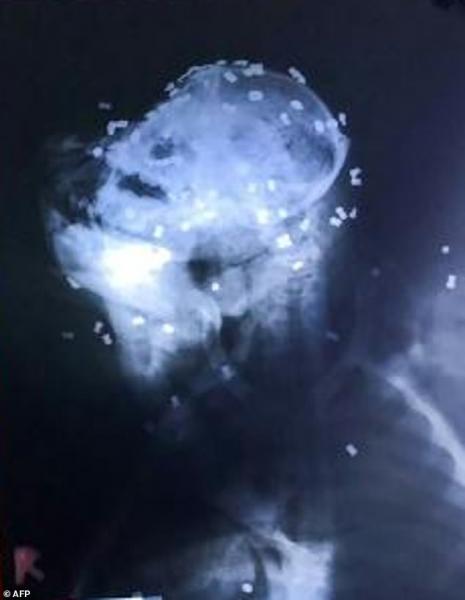

医生说,这只濒危大猩猩年龄在5到7岁之间。X光片显示,这只大猩猩身中130发气枪子弹,仅头部就有74颗,其余分散在身体其它部位。另外,这只大猩猩身上还有多处刀伤,眼睛也被打瞎。